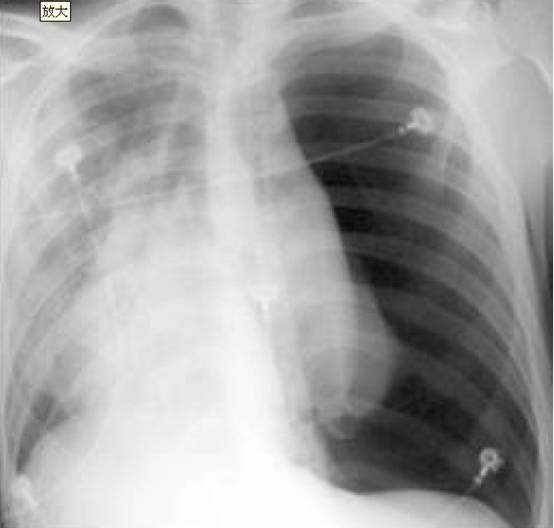

1. 20岁男性因“呼吸困难半小时”来诊,伴有大汗、心悸。胸片如图

考虑诊断:

A. 右侧肺炎

B. 左侧肺栓塞

C. 左侧气胸

D. 右侧肺不张

答案:1. C; 2. B; 3. C; 4.B